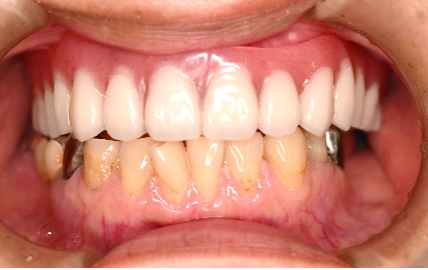

Before

赤丸は抜歯しました。上4本、下3本

【義歯を装着したところ】